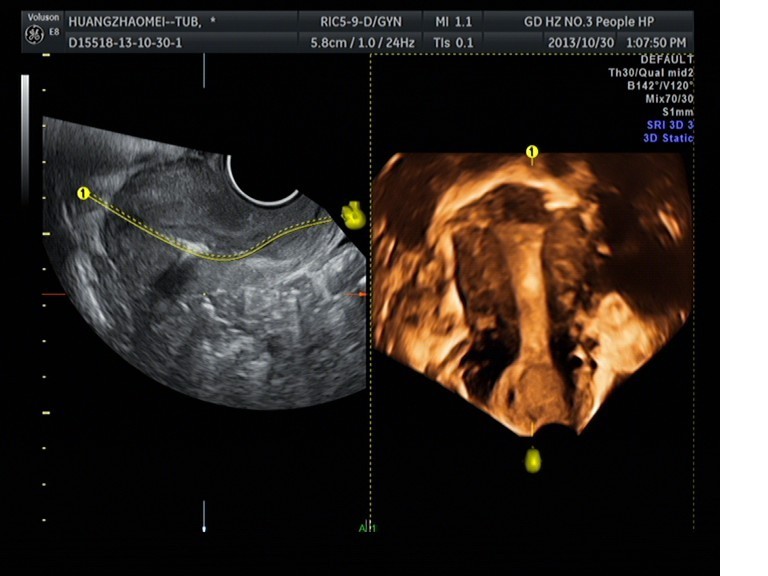

我院超聲科成功開(kāi)展子宮輸卵管超聲造影

隨著超聲醫(yī)療技術(shù)的發(fā)展日新月異,超聲在臨床中不再只充當(dāng)輔助診斷的角色,也漸漸進(jìn)入了臨床治療階段,應(yīng)用范圍不斷擴(kuò)展。1030日上午,我院超聲科馬曉芹主任帶領(lǐng)自己的團(tuán)隊(duì)包括王瑤、邱藝瓊、楊君梅等醫(yī)生以及在婦產(chǎn)科王主任、盛主任、葉穎菲醫(yī)生的大力支持配合下成功完成開(kāi)展了首例子宮、輸卵管超聲造影術(shù)。這將是我院超聲科發(fā)展史上的一個(gè)重要里程碑,同時(shí)也標(biāo)志著我院婦產(chǎn)科在不孕不育的診斷方面上升到了一個(gè)新的臺(tái)階。

隨著四維超聲技術(shù)的成熟,隨著SonoVue 造影劑的誕生,經(jīng)陰道四維超聲聯(lián)合應(yīng)用SonoVue 超聲造影檢查子宮、輸卵管的技術(shù)也應(yīng)運(yùn)而生。子宮輸卵管超聲造影術(shù)具有無(wú)放射性、不需特殊環(huán)境、無(wú)過(guò)敏反應(yīng)、可重復(fù)檢查、無(wú)損傷性、安全、價(jià)廉等優(yōu)點(diǎn),容易顯示輸卵管全程、對(duì)輸卵管盤(pán)曲或成角的判斷更精確,降低操作依賴(lài)性,操作簡(jiǎn)便,圖像直觀,便于臨床醫(yī)師觀察。這既彌補(bǔ)了以往輸卵管通液術(shù)的主觀性較大、準(zhǔn)確性較差等不足,更避免了X 線(xiàn)子宮輸卵管碘油造影(HSG)的射線(xiàn)輻射、碘油過(guò)敏以及腹()腔鏡檢查有創(chuàng)傷高風(fēng)險(xiǎn)等缺點(diǎn)。

目前,我院超聲科已具備實(shí)施該項(xiàng)檢查的設(shè)備及臨床技術(shù)支持。它通過(guò)宮腔內(nèi)注射SonoVue 超聲造影使宮腔及輸卵管顯影,可清楚觀察到宮腔、宮角、雙側(cè)輸卵管全程的形態(tài)及與卵巢的位置關(guān)系。子宮輸卵管超聲造影術(shù)的成功開(kāi)展,將大大解除不孕患者的痛苦及消除他們的心理陰影,真正地給每一對(duì)不孕夫婦帶來(lái)福音、帶來(lái)家庭的幸福! 超聲科 馬李明)